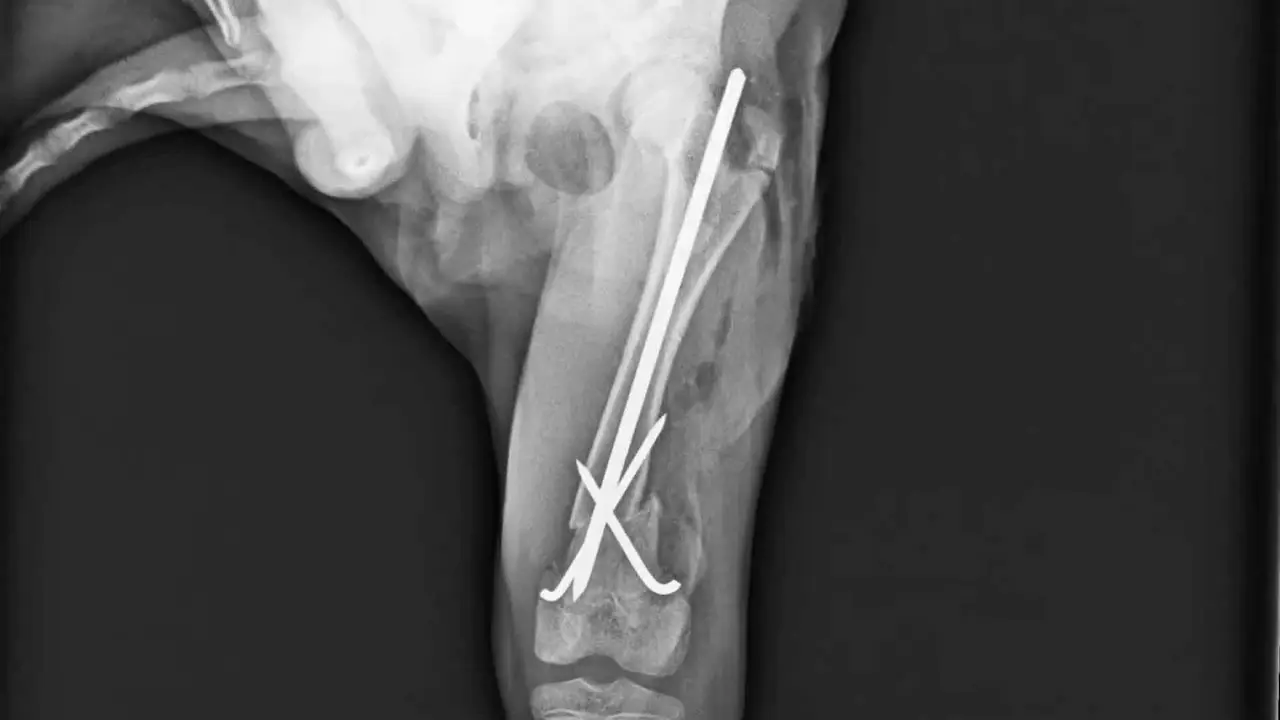

Cuando el examen físico sugiere fractura, el siguiente paso es la confirmación mediante estudios radiográficos. La radiología permite identificar con precisión el hueso y la articulación afectados, valorar la posición de los fragmentos y clasificar la fractura como simple o compleja, lo cual resulta determinante para definir el plan terapéutico. Tal y como señalan las guías de la American College of Veterinary Surgeons (ACVS), las fracturas de fémur rara vez se tratan de forma conservadora y, en la mayoría de los casos, la estabilización quirúrgica es la opción recomendada, ya que asegura una correcta alineación ósea y reduce de manera significativa el riesgo de complicaciones como consolidaciones defectuosas o pseudoartrosis.

- Osteosíntesis con placas y tornillos: indicada en fracturas diafisarias o metafisarias, asegura una estabilidad rígida y permite una recuperación más temprana de la función.

- Clavos intramedulares: útiles en fracturas simples de diáfisis, aunque ofrecen menor control rotacional y requieren complementarse a veces con cerclajes.

- Fijadores externos: recomendados en fracturas abiertas o altamente conminutas, donde el riesgo de infección obliga a mantener un acceso fácil para el cuidado posoperatorio.

La literatura clínica señala que el uso de técnicas combinadas (placa + tornillo bloqueado, o clavo + fijador externo) puede mejorar la estabilidad en fracturas complejas. Según el American College of Veterinary Surgeons (ACVS), la cirugía temprana reduce la probabilidad de consolidación viciosa y acelera el retorno funcional.